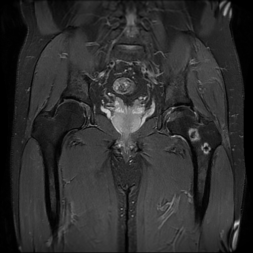

术前各学科各司其职、精心筹备,在徐永清教授带领指导下给予患者行“术中给予左侧股骨头病损切除、减压、带骨方肌骨瓣移植术”,历时1小时,手术取得成功,患者安返病房,术后给予卧床休养、辅助专科药物,患者左髋疼痛及髋关节功能恢复良好,术后第十天出院。

术后MRI